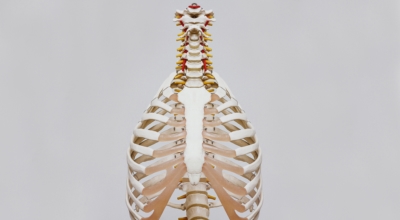

흉추와 복장뼈를 연결해서 가슴 전체를 둘러싸고 있는 가슴우리(흉강)을 형성하는 긴 곡선의 뼈를 말해요. 갈비뼈는 폐, 심장 등 내부 가슴 장기들을 지켜주고 가슴우리의 팽창과 수축으로 호흡을 도와주어요. 우리 몸은 총 12쌍의 갈비뼈를 갖고 있어요. 1~7번 갈비뼈는 복장뼈와 직접 관절로 연결되어 있어 참갈비뼈라고 하며, 8~12번 갈비뼈는 거짓 갈비뼈라고 하는데 거짓 갈비뼈 중 8, 9, 10번 갈비뼈는 하나의 연골을 통해 복장뼈와 연결되어 있고 나머지 11~12번째 갈비뼈는 뜬갈비뼈로 복장뼈와 연결되어 있지 않아요.